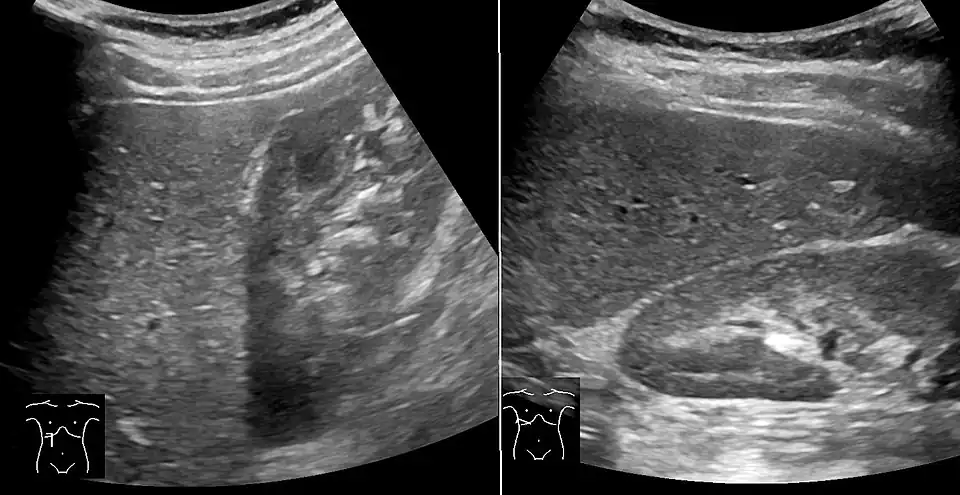

Abdominal ultrasonography with the liver and kidney side by side (left image) may give a false impression of hyperechogenic liver, so it's preferably done with the organ borders facing the ultrasound probe (right image, of the same case). -